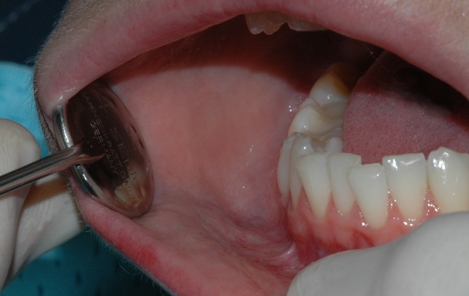

Etter undersøkelsen er det vanlig at tannlegen eller tannpleieren fjerner tannstein og misfarging fra tennene. Tannstein består for det meste av kalkstoffer fra spyttet som avleires og legger seg på tannflaten som et hardt belegg. Det sitter så godt fast at det er nærmest umulig å fjerne på egen hånd med tannbørsten.

Mye av det vi inntar i det daglige kan misfarge tennene. Dette gjelder for eksempel kaffe, te, røyk, snus og rødvin. Slike misfarginger legger seg som et mørkt belegg på tennenes overflate og kan også være vanskelige å fjerne selv.

Tannlegen eller tannpleieren kan fjerne både tannstein og overfladiske misfarginger ved å rense, pusse og polere tennene. Tannsteinen fjernes enten med maskin eller ved å skrape den bort med håndinstrumenter. Misfarginger kan poleres bort med en spesiell pussepasta som inneholder ekstra slipemiddel. Alternativt går det an å benytte saltblåsing for å fjerne misfargingene.